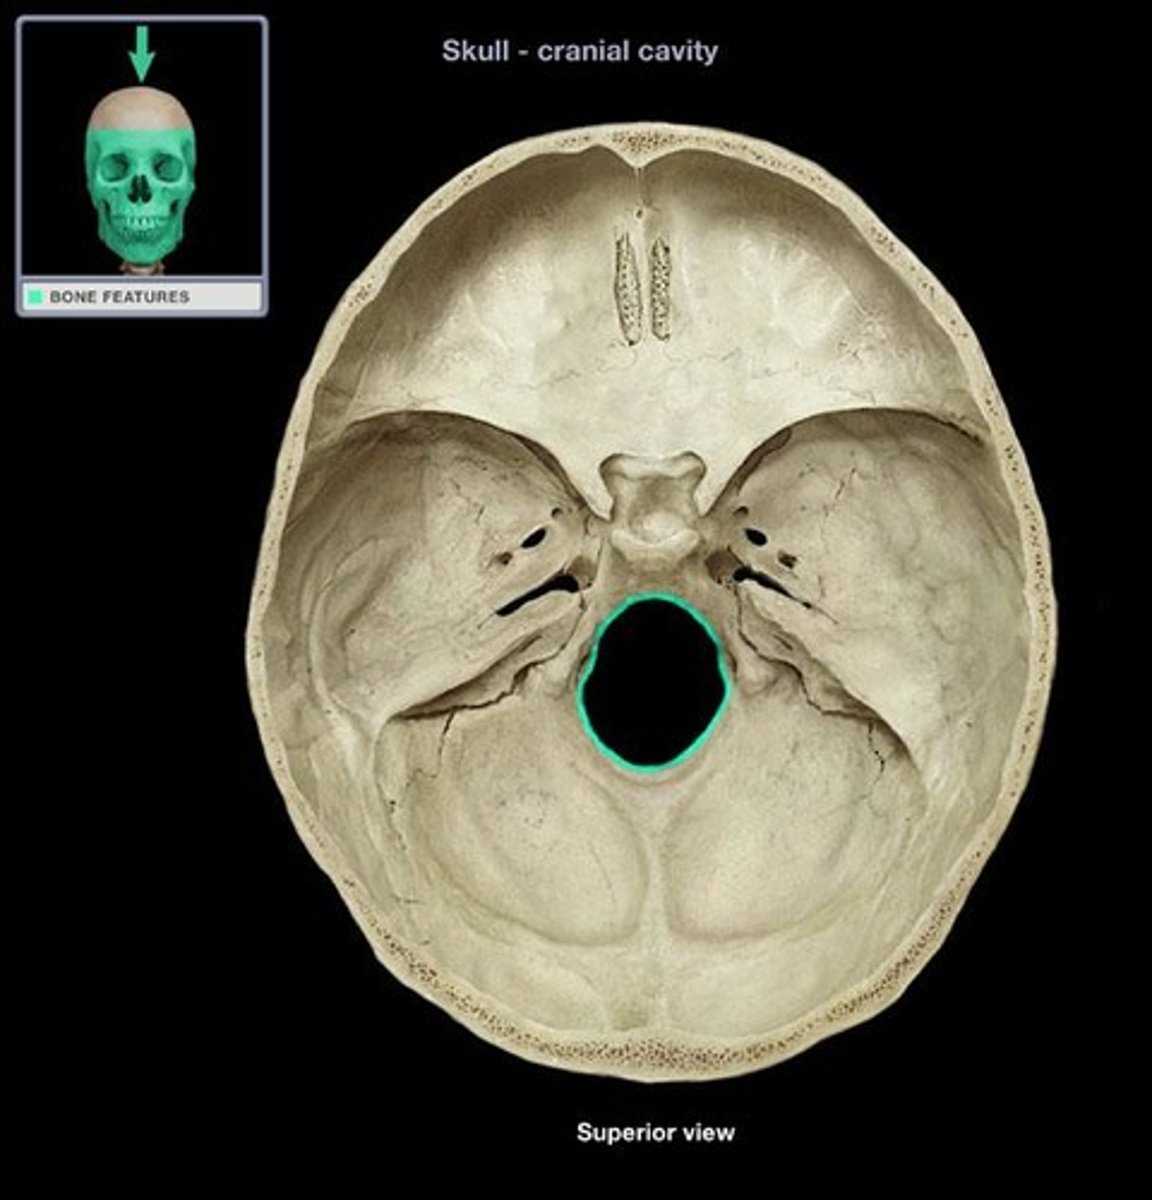

foramen magnum of occipital bone

opening through which spinal cord connects to lower brain

posterior cranial fossa

portion of cranial canal formed by the occipital